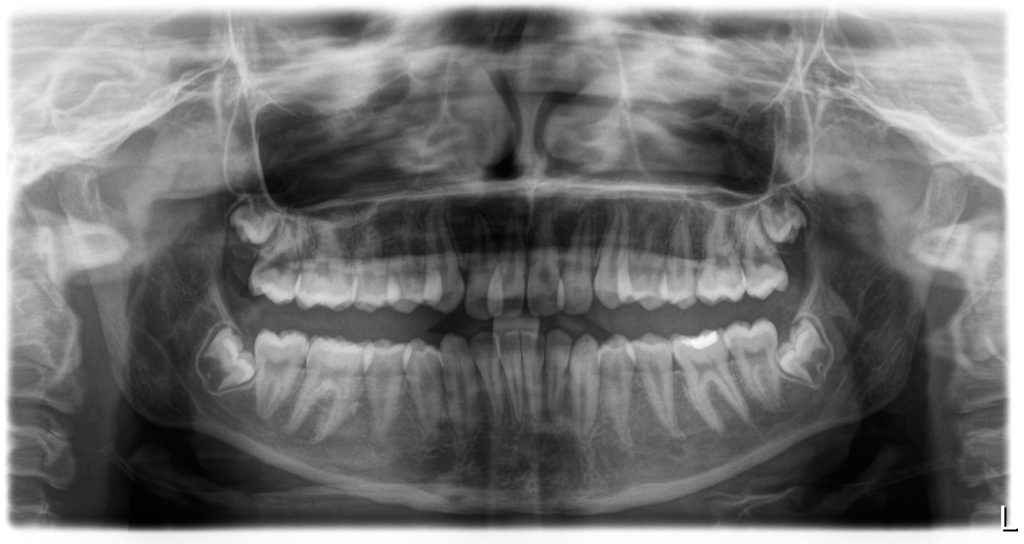

- Front teeth that didn’t meet (open bite)

- Narrow upper jaw (palate)

A combination of clinical evaluation, radiographs, and functional tests revealed that it was both anatomical and habitual — a dual problem.

- Mild enlargement of adenoids causing partial obstruction

- Narrow palate and open bite

Follow-up imaging and ENT review showed that the adenoids had reduced naturally.